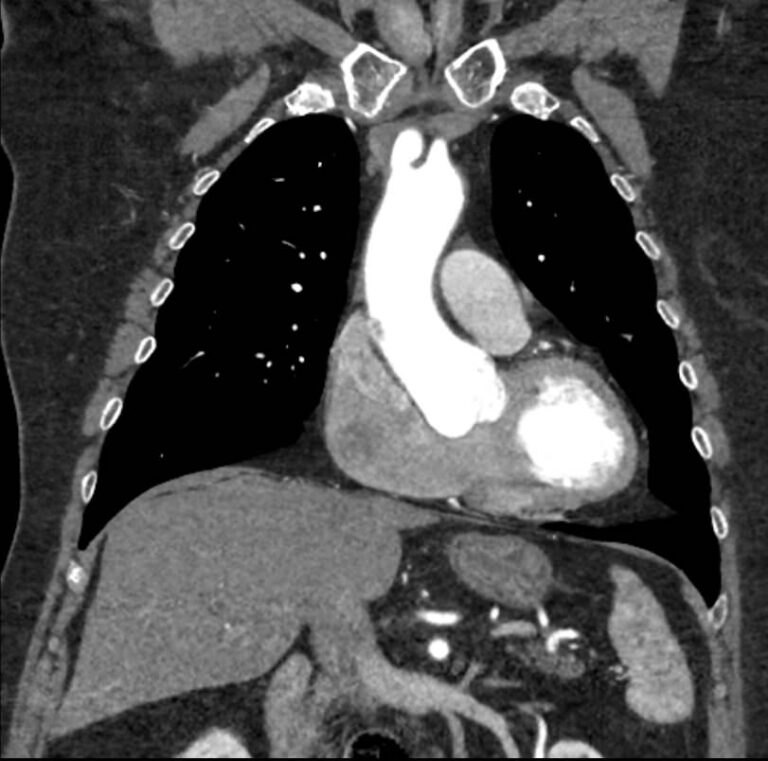

Грудная аорта делится на несколько отделов – восходящий отдел аорты, дуга аорты и нисходящий отдел. Корень аорты отходит непосредственно от левого желудочка, в его состав входят синусы Вальсальвы от которых берут начало коронарные артерии. После корня, прослеживается тубулярная часть восходящего отдела аорты, которая переходит в дугу аорты.

Дуга аорты дает начало брахиоцефальным артериям, которые питают головной мозг и верхние конечности. Затем следует нисходящий отдел аорты, распространяющийся через отверстие в диафрагме. От грудного отдела аорты отходят висцеральные артерии, кровоснабжающие органы средостения: бронхиальные, пищеводные, перикардиальные, медиастинальные артерии.

Одним из информативных методов диагностики сосудистой патологии является мультиспиральная компьютерная томография грудной аорты и ее ветвей (КТ-ангиография). Метод сканирования при помощи рентгеновских лучей и цифровой обработки данных позволяет получать послойные снимки сосудов и трехмерные реконструкции сосудистой системы в мельчайших подробностях.

Для того, чтобы качественно визуализировать сосудистую систему КТ-ангиография предусматривает в обязательном порядке применение контрастного усиления. Йодсодержащее контрастное вещество вводится пациенту внутривенно и, благодаря способности контраста поглощать рентгеновские лучи, ярко контрастирует сосудистую систему на фоне окружающих тканей.

КТ-ангиография позволяет диагностировать аневризмы аорты, сосудистые аномалии развития, воспалительные изменения стенок сосудов, пристеночные тромбы, сужения просвета сосудов за счет сдавления извне близлежащими опухолевыми образованиями.

В медицинских центрах «Доступная медицина» КТ сканирование грудной аорты и ее ветвей проводится на новейших мультиспиральных компьютерных томографах экспертного уровня TOSHIBA AQUILION. Современные технологии мультисрезового сканирования обеспечивают высокое качество изображений при уменьшенной дозе облучения для пациента. Это делает КТ-ангиографию высокоинформативным быстрым методом диагностики сосудистой патологии. Процедура не требует вмешательства в организм пациента и может проводится для скринингового обследования с целью раннего выявления патологии грудного отдела аорты.